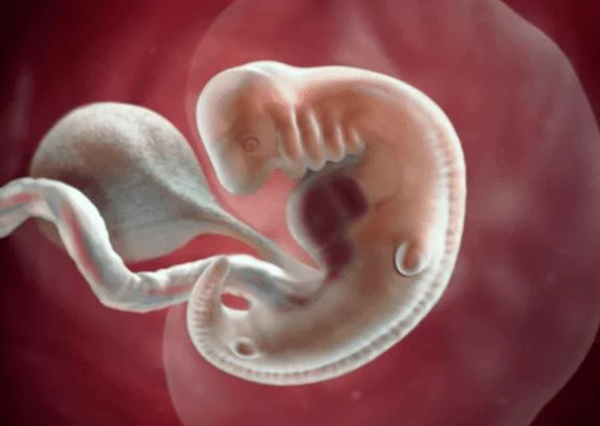

Để biết được tuần thứ mấy có tim thai thì trước hết mọi người cần phải hiểu sơ qua về sự hình thành của tim thai như thế nào? Thông thường tim thai sẽ bắt đầu xuất hiện và dần hình thành ở ngày thứ 15,16 của thai kỳ. Trường hợp khi phôi thai xuất hiện với 2 mạch máu đây chính là đang hình thành ống dẫn tim.

Ống dẫn này đến thời điểm cuối của tháng đầu tiên thì chúng sẽ dài thêm khoảng 1cm. Và đây cũng là thời điểm mà tim thai đang dần bắt đầu hoàn thiện. Còn bước sang thời điểm tháng thứ 2 khoảng tuần đầu tiên thì một số bộ phận khác của bé cũng sẽ phát triển như cột sống hãy não. Thời điểm này ở giữa của phôi thai sẽ xuất hiện một hạt rất nhỏ và chúng sẽ dần dần phát triển trở thành tim thai. Vì vậy ở thời điểm này các mẹ nếu đi khám thai cũng dễ dàng nghe được tim thai.

Thời điểm tiếp theo khoảng tuần thứ 7 của thai kỳ tim thai sẽ ngày một phát triển hơn. Chúng sẽ phân chia thành các buồng tim trái và phải. Và khoảng tới 5 tuần tiếp theo thì tim thai sẽ hoàn thiện một cách đầy đủ nhất.